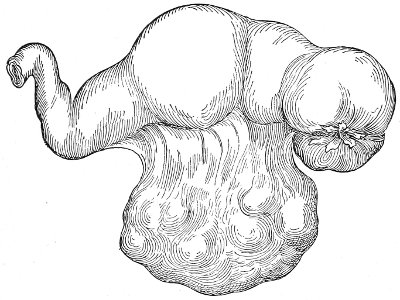

Suppuration of the vulvo-vaginal gland is accompanied by marked swelling and peripheral edema. The swelling may extend to the anus, and is of characteristic shape (Fig. 17). The pain is always severe. Fluctuation is first apparent on the inner surface of the labium majus. If the condition is not treated, one or more fistulous openings appear below the orifice of the duct, and the pus is discharged. The condition then becomes chronic. The fistulous openings persist. Acute inflammation disappears from the gland, leaving it in a condition of hypertrophic induration. A thin, milky or greenish, purulent fluid may be pressed out of the duct or the fistulous openings. Infection from this discharge may be communicated to man, or may ascend the genital 40 tract, producing inflammation of the endometrium or of the Fallopian tubes.

Fig. 17.—Abscess of right vulvo-vaginal gland.